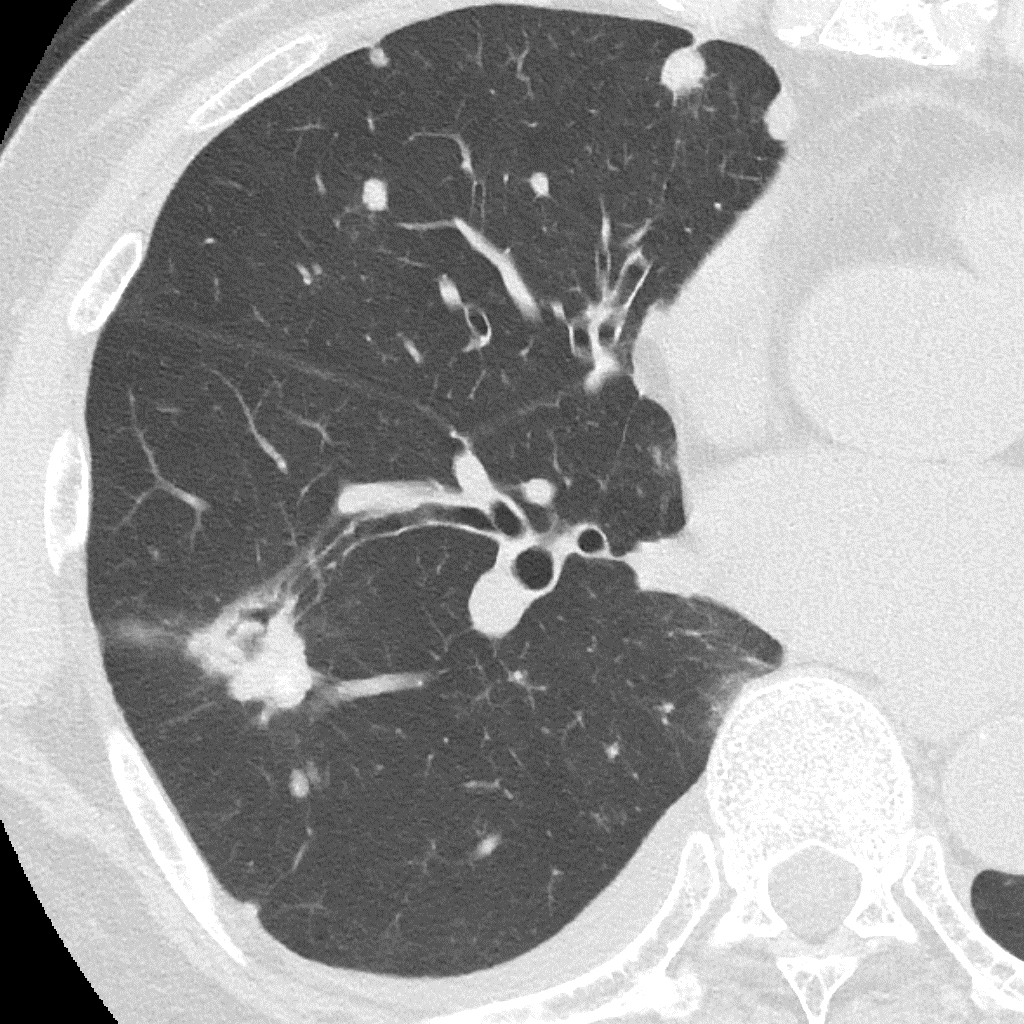

Порівняння звичайної роздільної здатності з ультрависокою роздільною здатністю (УРЗ)²

Звичайна КТ 0,5 мм

КТ з ультрависокою роздільною здатністю 0,25 мм ³